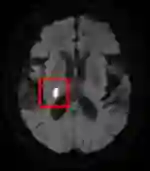

Stroke is a common disabling neurological condition that affects about one-quarter of the adult population over age 25; more than half of patients still have poor outcomes, such as permanent functional dependence or even death, after the onset of acute stroke. The aim of this study is to investigate the efficacy of diffusion-weighted MRI modalities combining with structured health profile on predicting the functional outcome to facilitate early intervention. A deep fusion learning network is proposed with two-stage training: the first stage focuses on cross-modality representation learning and the second stage on classification. Supervised contrastive learning is exploited to learn discriminative features that separate the two classes of patients from embeddings of individual modalities and from the fused multimodal embedding. The network takes as the input DWI and ADC images, and structured health profile data. The outcome is the prediction of the patient needing long-term care at 3 months after the onset of stroke. Trained and evaluated with a dataset of 3297 patients, our proposed fusion model achieves 0.87, 0.80 and 80.45% for AUC, F1-score and accuracy, respectively, outperforming existing models that consolidate both imaging and structured data in the medical domain. If trained with comprehensive clinical variables, including NIHSS and comorbidities, the gain from images on making accurate prediction is not considered substantial, but significant. However, diffusion-weighted MRI can replace NIHSS to achieve comparable level of accuracy combining with other readily available clinical variables for better generalization.